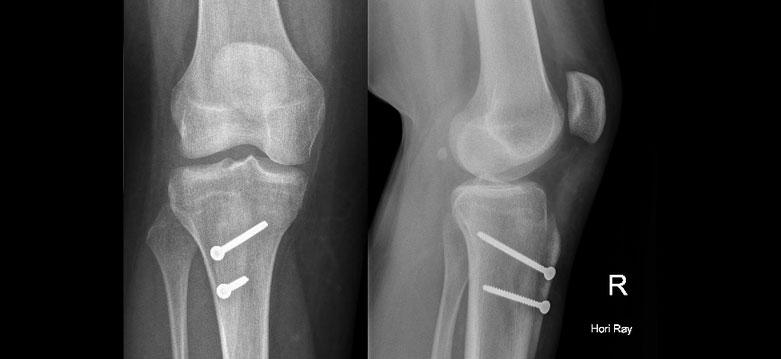

Severe injuries are universally treated surgically. Any fractures fixed, and then either one or two screws, or a suture construct between the two bone. If there is no fracture, usually the medial ankle ligament is torn. There is no clear superior technique, but untreated, 100% of the body weight goes through the top of the talus, where as normally, 40% of the weight is transmitted through the malleoli. Where screw fixation is used, it is often left in place three months, but walking permitted before the screw is removed.

An XR demonstrating the talus shifted away from the tibia – the medial ligament, and both the AITFL and PITFL are torn. This should be aggressively treated.

This injury was fixed with a screw. DJM allows the patients to fully weight bear at six weeks. Typically the screw is removed about three months from insertion. If the screw breaks, the minor irritation the patient can feel caused by the syndesmosis being too rigid resolves. Sometimes the patient chooses to leave the screw permanently.